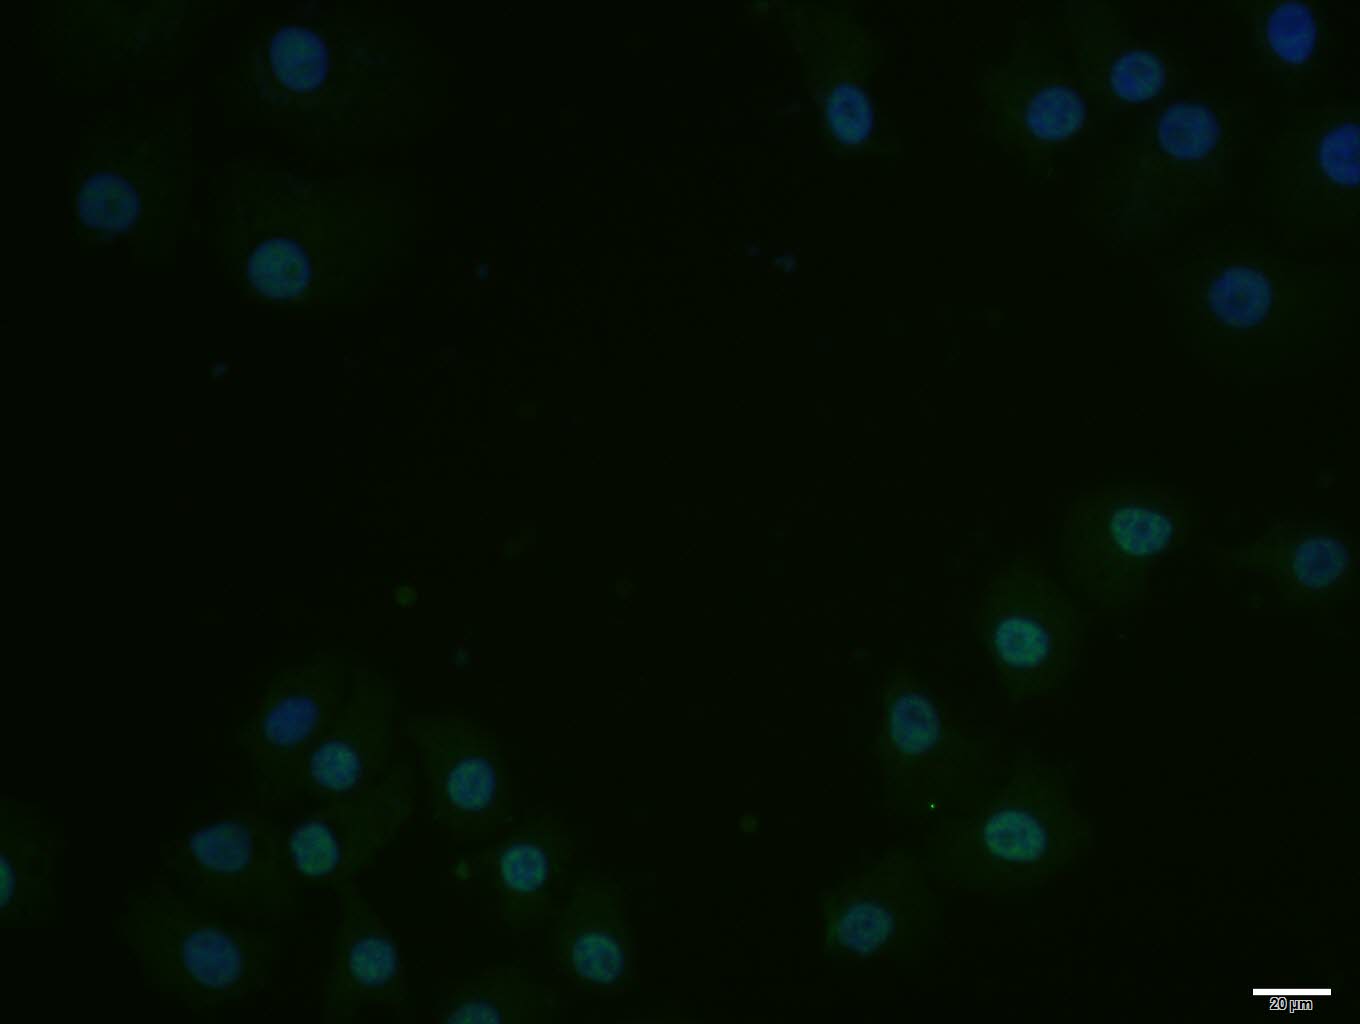

A431 cell; 4% Paraformaldehyde-fixed; Triton X-100 at room temperature for 20 min; Blocking buffer (normal goat serum, C-0005) at 37°C for 20 min; Antibody incubation with (Cdc25C) polyclonal Antibody, Unconjugated (bs-10579R) 1:100, 90 minutes at 37°C; followed by a conjugated Goat Anti-Rabbit IgG antibody at 37°C for 90 minutes, DAPI (blue, C02-04002) was used to stain the cell nuclei.

Hela cell; 4% Paraformaldehyde-fixed; Triton X-100 at room temperature for 20 min; Blocking buffer (normal goat serum, C-0005) at 37°C for 20 min; Antibody incubation with (Cdc25C) polyclonal Antibody, Unconjugated (bs-10579R) 1:100, 90 minutes at 37°C; followed by a conjugated Goat Anti-Rabbit IgG antibody at 37°C for 90 minutes, DAPI (blue, C02-04002) was used to stain the cell nuclei.

HepG2 cell; 4% Paraformaldehyde-fixed; Triton X-100 at room temperature for 20 min; Blocking buffer (normal goat serum, C-0005) at 37°C for 20 min; Antibody incubation with (Cdc25C) polyclonal Antibody, Unconjugated (bs-10579R) 1:100, 90 minutes at 37°C; followed by a conjugated Goat Anti-Rabbit IgG antibody at 37°C for 90 minutes, DAPI (blue, C02-04002) was used to stain the cell nuclei.